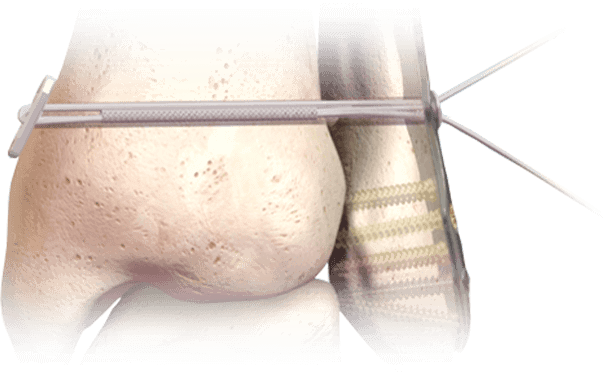

Hercules® Knotless Syndesmosis Implant System

A low-profile, knotless alternative to rigid screw fixation for syndesmotic injuries and midfoot stabilization.

Applications:

- Syndesmosis disruptions (Weber B/C ankle fractures)

- Adjunct to hallux valgus correction

- Midfoot and forefoot joint stabilization

Key Advantages:

- UHMWPE suture tensioned between low-profile titanium alloy buttons

- Allows micromotion to support natural healing biomechanics

- Delivered in a sterile, single-use kit

- Compatible with plate or standalone use